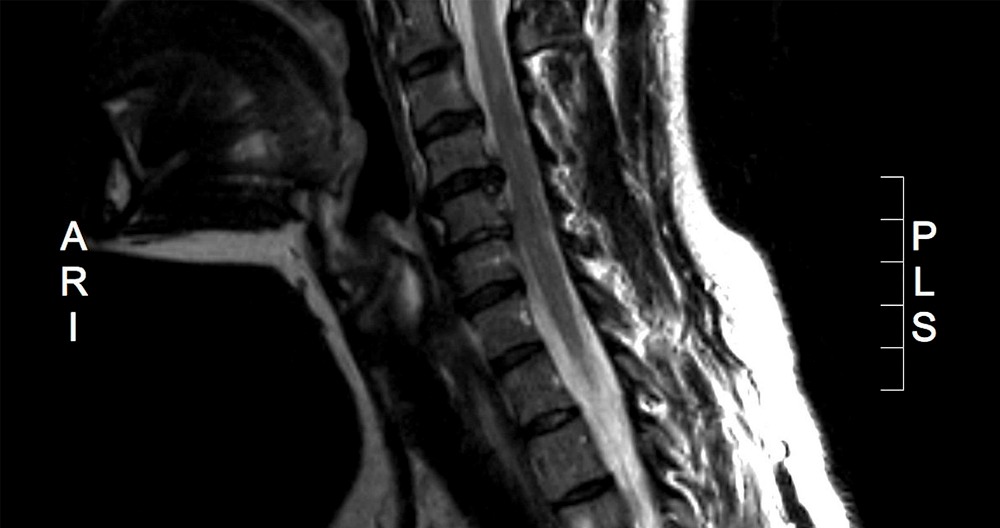

Herniated Cervical Disc MRI

MRI scans are the most non-invasive way to detect bulging and herniated discs. With an MRI scan doctors can pinpoint herniated discs in their spine with over 95% accuracy due to the high spatial resolution of the spinal anatomy.

MRI scans can be used to diagnose and monitor herniated discs. They are most commonly used to determine the location of herniated discs in the spine and determine the extent of nerve compression. Your doctor may recommend additional tests if the MRI results show a herniated disc. MRIs can be used to diagnose bulging discs or herniated discs in the neck or back.

An MRI scan image generated by the scanner shows anatomy. It distinguishes between tissues that have a lot of water (such cerebrospinal fluid, discs, or other fluids) and those with less water (such skin, bone, cartilage and nerve roots). Your doctor will inspect the image for any abnormalities to diagnose your condition. MRI scans can detect disc injuries like a bulging disc, bulging disc, or annular tear that causes back pain or pinched nerve.

How to read an MRI of a Herniated Disc

A lumbar MRI scan of a herniated disc will be accurate if the patient has a basic understanding about the anatomy of the lumbar spine. There are five components to the lower back. They are separated by two types of joint, facet and discs. These discs are often in constant motion, which causes wear and tear. An annular tear is when the outer disc layer ruptures and the inner nucleus jelly of the disc pushes into the spinal canal, forming a hernia. An MRI scan will often reveal this hernia as a contrast spot.